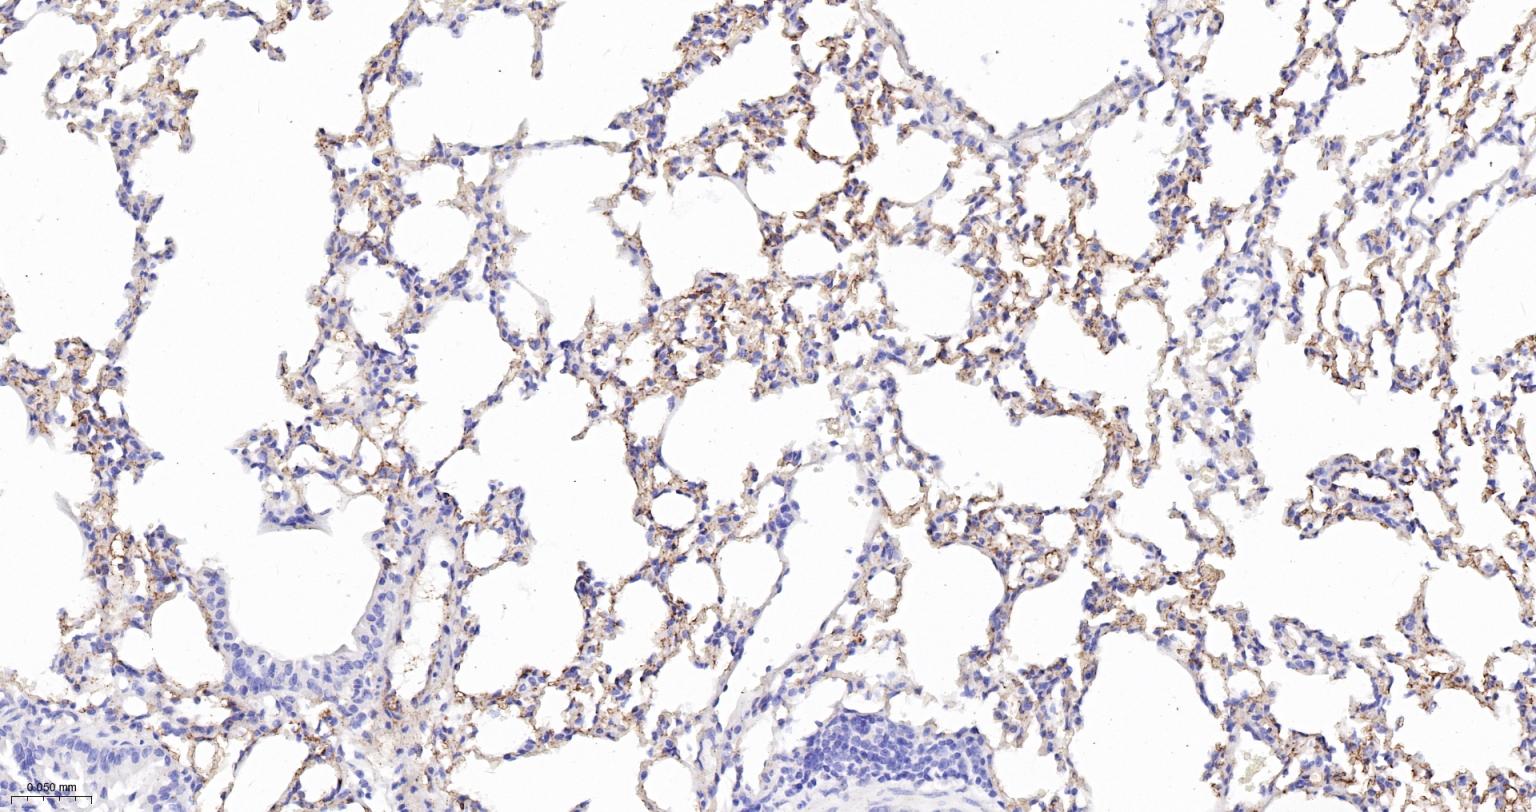

Paraformaldehyde-fixed, paraffin embedded Mouse lung; Antigen retrieval by boiling in sodium citrate buffer (pH6.0) for 15 min; Antibody incubation with ACE Monoclonal Antibody, Unconjugated(bsm-61652R) at 1:200 overnight at 4°C, followed by conjugation to the bs-0295G-HRP and DAB (C-0010) staining.